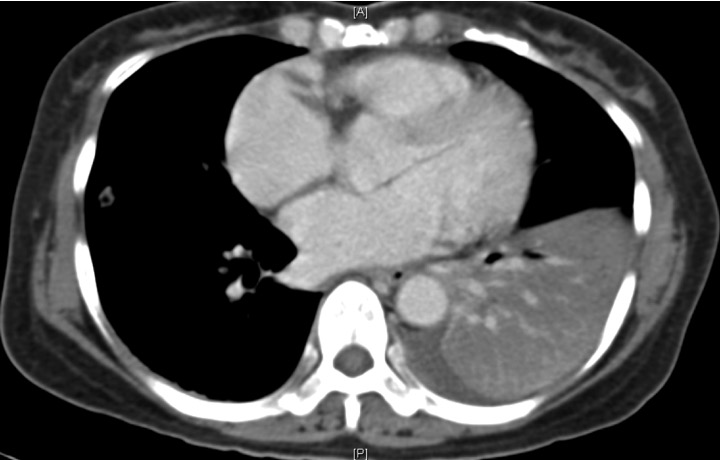

Her antibiotic therapy was escalated to IV imipenem with IV gentamicin, and a CT thorax was arranged (Figure 2 below), which showed dense consolidation of the left lower lobe.

This is currently a rare clinical presentation, but nonetheless “classical”. Most clinicians would assume that invasive fungal infections (IFIs) would be high on the cards, given the profound neutropenia and antibiotic coverage. However, it is extremely unusual for IFIs to present so acutely, with actual clinical deterioration and de-saturation on just the 4th day of febrile neutropenia. The large consolidation seen on the CT thorax is also very atypical of an IFI, which usually appears as nodules – occasionally with “crescent” and “halo” signs – on CT.